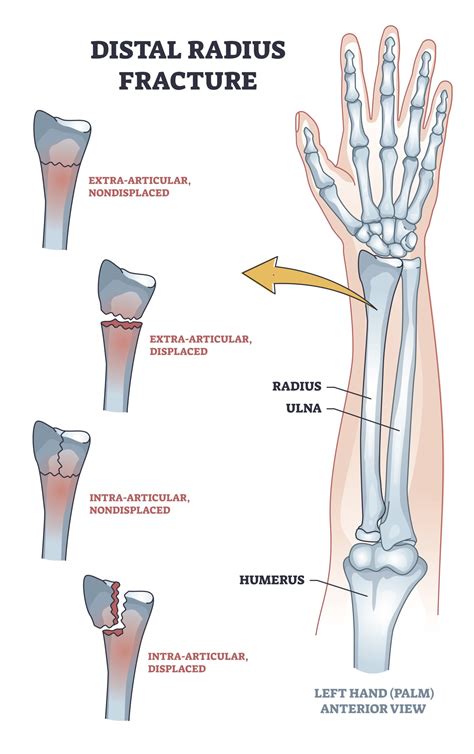

Displaced vs. Non-Displaced Fractures

Fractures can be displaced or non-displaced:

• Non-Displaced Fractures: In a non-displaced fracture, the bone breaks but the pieces remain aligned. These fractures are generally easier to treat and heal more quickly.

• Displaced Fractures: In a displaced fracture, the bone breaks and the pieces shift out of alignment. These fractures often require surgical intervention to realign the bone fragments.

• Wrist Fractures: Wrist fractures, often referred to as Colles' fractures, are common in older adults and often result from falls onto an outstretched hand. These fractures can be treated with immobilization, such as casting or splinting.